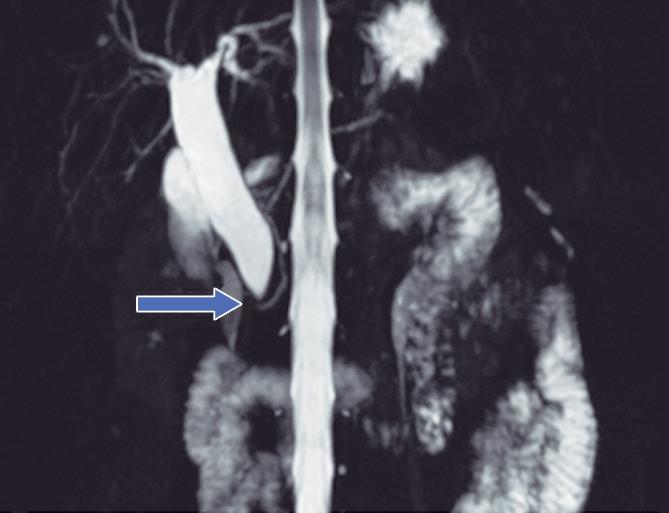

Hipoplasia pancreática

La agenesia pancreática completa es incompatible con la vida y extremadamente infrecuente. La agenesia parcial o hipoplasia puede involucrar el brote ventral o dorsal, con mayor frecuencia este último. Puede ser una condición aislada o bien estar asociada al síndrome de heterotaxia - poliesplenia. En la hipoplasia del páncreas dorsal se observa la porción cefálica y el proceso uncinado de aspecto redondeado, con ausencia del cuello, cuerpo y cola. Suele observarse relativa prominencia

del proceso uncinado, que se prolonga por detrás de los vasos mesentéricos (Figura 15). Es imprescindible efectuar el diagnóstico diferencial y descartar exhaustivamente una lesión neoplásica que provoque atrofia del páncreas corpocaudal, distal al tumor. Los individuos con agenesia del páncreas dorsal suelen ser asintomáticos, aunque se ha descripto un riesgo incrementado de padecer diabetes debido a que el mayor porcentaje de los islotes de células de Langerhans se hallan en el páncreas distal. 27

parcial del brote dorsal)

A) Resonancia magnética, secuencia T2, plano coronal. Se observa un páncreas “truncado”, con ausencia de tejido glandular a la izquierda del cuello (flecha), coincidente con una agenesia parcial del brote embriológico dorsal. La cabeza de flecha nos muestra a la porción cefálica prominente, redondeada. B) Resonancia magnética, secuencia T1 con contraste, plano axial. Flecha: Limite de finalización de la glándula, a la izquierda de la arteria mesentérica superior. Cabeza de flecha: Porción cefálica prominente, redondeada. C) Resonancia magnética, secuencia T1 con contraste, plano axial, corte más caudal. Las flechas muestran hipertrofia relativa del proceso uncinado (brote ventral), el cual llega a ubicarse por detrás de los vasos mesentéricos superiores, incluso superando el plano de la arteria. AMS: arteria mesentérica superior.